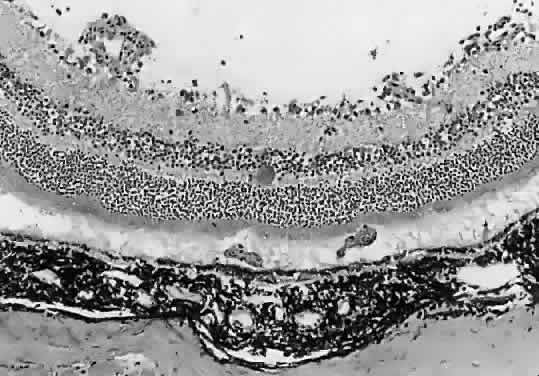

The expense and inconvenience of using nonhuman primates led to the renewed interest in rodent models of disease. Pavesio and associates54 were able to produce multifocal toxoplasmic retinochoroiditis in hamsters consistently after intraperitoneal inoculation of the ME49 strain of T gondii. Animals develop multiple foci of retinitis that resolve spontaneously without treatment. After resolution of lesions, tissue cysts can be found in the retina (Fig. 3). This model may prove to be useful for the study of T gondii infections of the retina at a cellular level and may ultimately be useful for studying the efficacy of cysticidal drugs as they become available. This model will be less useful for studying the natural history of human disease, however, because the number, distribution, and appearance of lesions are not reminiscent of those seen in human beings.

Fig. 3. Light micrograph of a hamster eye after resolution of ocular toxoplasmosis. A large tissue cyst is seen in normalappearing retina (hematoxylin and eosin). (Courtesy of Barbara A. Nichols, PhD.)